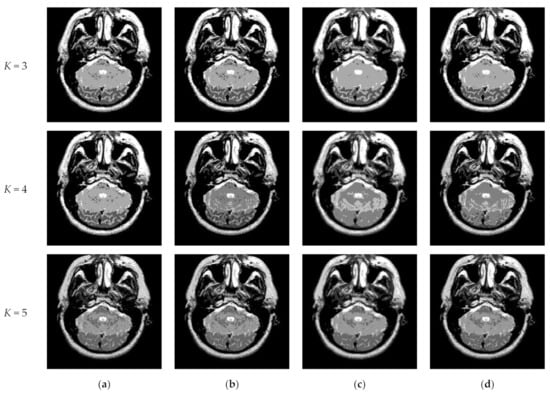

Figure 10 and Figure 11 display segmentation results of different algorithms for slice #042 and slice #082, respectively. For single level of thresholding K = 1, it can be observed that segmentation results obtained by the Otsu method have many fragmented small areas, such as the lower soft tissue in the first row of Figure 10a, whereas IIMT performs slightly better. However, the edges segmented by HL-IIMT and Proposed are much clearer. In the case of , it can be seen that Otsu and IIMT have similar segmentation effects. HL-IIMT and Proposed are better than Otsu and IIMT in terms of edge-preserving and denoising, as shown in the segmentation results in Figure 11 (K = 2, K = 4).

Figure 10.

Segmentation results obtained by different segmentation algorithms for slice #042 with number of thresholds K from 1 to 5: (a) Otsu, (b) IIMT, (c) HL-IIMT, (d) Proposed.

Figure 11.

Segmentation results obtained by different segmentation algorithms for slice #082 with number of thresholds K from 1 to 5: (a) Otsu, (b) IIMT, (c) HL-IIMT, (d) Proposed.

Table 2 shows the values of uniformity measure (U) of Proposed, HL-IIMT, IIMT, and Otsu algorithms for slice #042 and slice #082. The best evaluation results are marked in bold. It can be noted that the U values achieved by Proposed are the highest for both of the two test images. To more clearly present the results, Figure 12 illustrates the comparison of U for different algorithms based on Table 2. In Figure 12, it can be clearly noted that Proposed achieves the highest values, and HL-IIMT comes second, followed by IIMT and Otsu. This indicates that the novel thresholding method IIMT presented in this paper is effective, and our Proposed based on IIMT can obtain satisfactory segmentation results with clear edges and little noise.